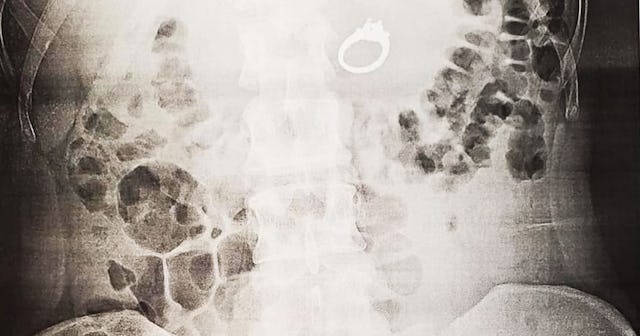

The post goes on to describe a trip to urgent care, an x-ray, and eventually, a relatively minor surgery. Finally, the ring was back on the outside. After that, Bobby took her to get some real food and finally allowed her to have her ring back. “I promised not to swallow it again, we’re still getting married and all is right in the world,” she wrote.